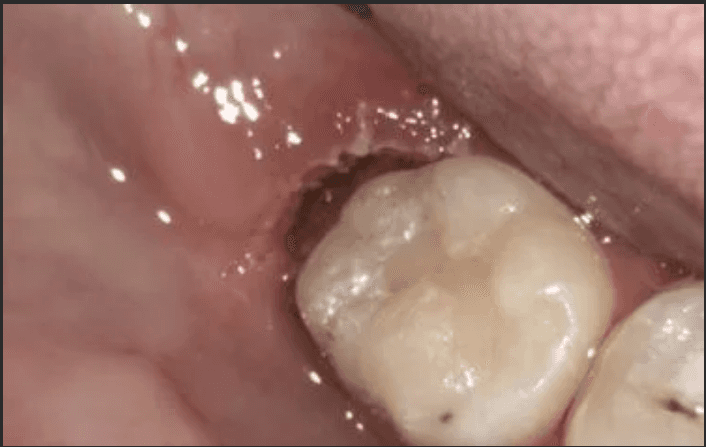

A 25-year-old woman accidentally bit into the thin collar of gum sitting over her lower right wisdom tooth and wanted to consider extraction. Despite being a wisdom tooth, it was a functional tooth with an opposing wisdom tooth to bite against. It was an issue with overlying gum, rather the wisdom tooth itself. After removing the collar of gum, it recovered well without recurrence and she has managed to keep the wisdom tooth to present day without any further issues.

During